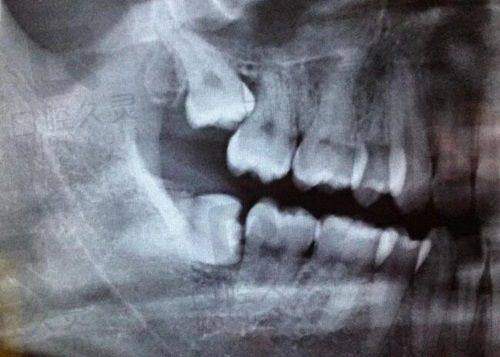

曾经有一位患者,由于长期缺牙导致牙槽骨重度萎缩,特别多医院都认为种植难度太大而拒绝了他。金华旦博士并没有轻易放弃,他运用精良的骨增量技术,精心为患者进行手术。在手术过程中,他凭借不错的技艺和高度的专注力,成功地为患者植入了种植体。术后,患者不仅修复得非常好,而且重新拥有了健康的牙齿,能够正常咀嚼食物,生活质量得到了极大的提升。

史立志院长擅长处理各种复杂的种植病例,对于高龄患者、患有系统性疾病的患者的种植手术也有着丰富的经验。他会在术前对患者进行全方面的评估,制定详细的手术计划,确保手术的安心和成功。在手术过程中,他操作熟练、精细,能够较大程度地减少患者的痛苦和创伤。